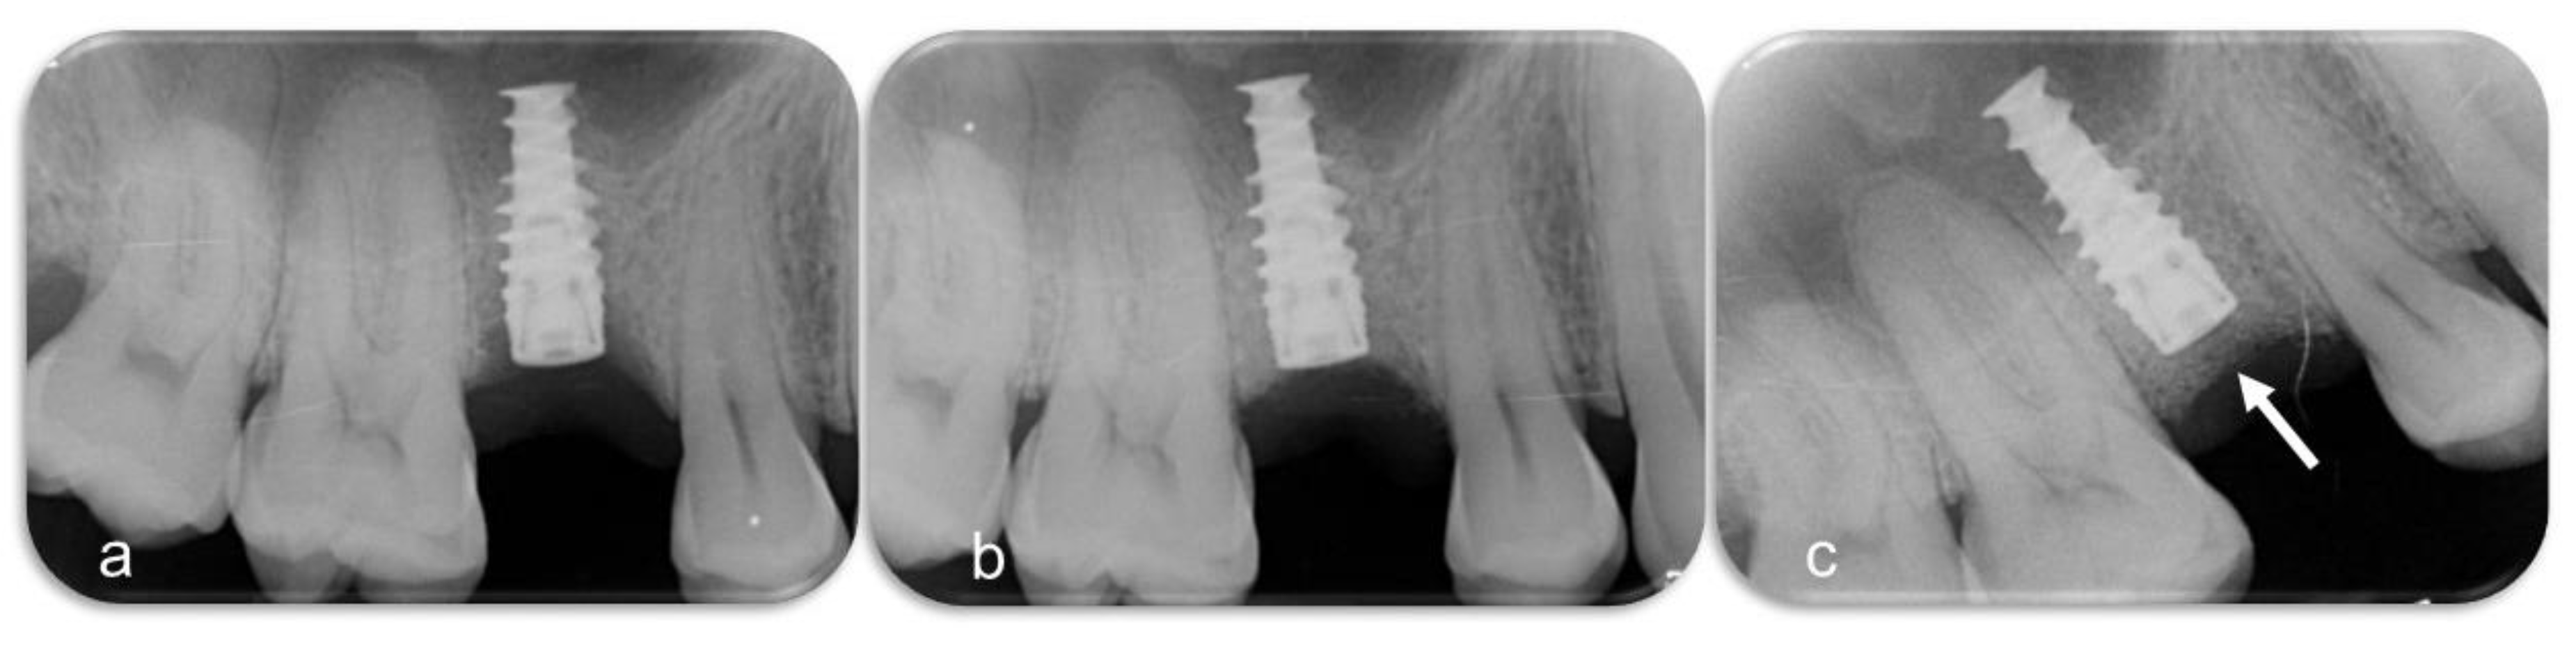

2.3. Devices and Mode of Action